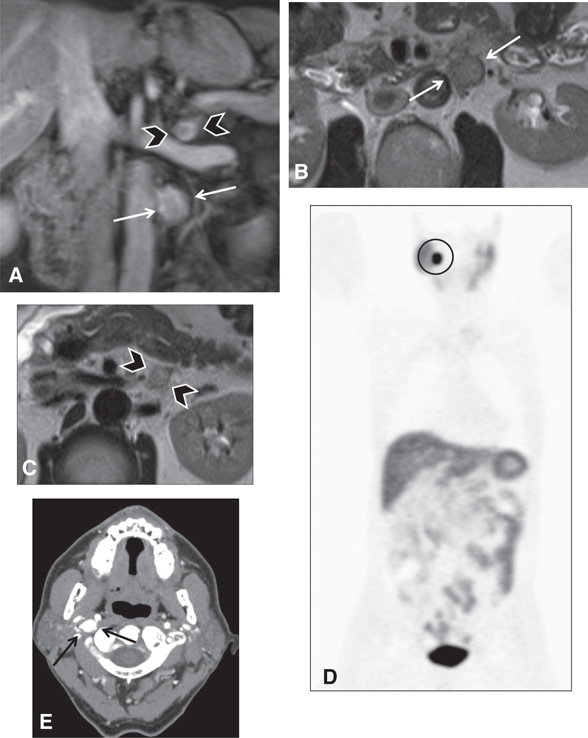

IMAGING INDICATIONS

PPGLs can arise in various parts of the body, but they are classified by anatomic location into intra-adrenal and extra-adrenal sites. In contrast to head and neck paragangliomas, abdominal or trunk PPGLs arise from thoracic and abdominal sympathetic ganglia, producing catecholamines (8, 9). Imaging can be utilized at different stages of PPGL disease course. Diagnostic imaging for screening purposes can be offered for patients with germline mutations and high-risk syndromes (Figure 1), such as multiple endocrine neoplasia (MEN) types 2 and 3, von Hippel-Lindau (VHL), neurofibromatosis type 1 (NF1), and succinate dehydrogenase (SDH) mutations (10). This can be done with whole body positron emission tomography (PET) combined with computed tomography (CT) or magnetic resonance imaging (MRI) as in PET/CT or PET/MRI, or with anatomic imaging alone such as MRI or CT of the abdomen and pelvis. The frequency of imaging usually depends on the patient’s age and the specific underlying mutation or syndrome.

Fig 1

Figure 1 Several neuroendocrine tumors in a 60-year-old male patient with succinate dehydrogenase (SDH) subunit D mutation. (A, B, C) MRI of the abdomen demonstrates two left retroperitoneal lesions, one that is arising from the left adrenal gland (arrowheads) and a larger one more inferiorly, posterior to the fourth segment of the duodenum (white arrows) seen on (A) coronal fat-saturated post-contrast T1-weighted images and (B–C) fast spin echo T2 weighted images. The lesions were surgically resected. The left adrenal lesion was consistent with pheochromocytoma and the more inferior lesions were consistent with paraganglioma. (D) The patient underwent a gallium-68-DOTATATE scan to screen for additional neuroendocrine tumors. This demonstrated intense focal tracer uptake in the right neck (circle). (E) CT angiography and MRI of the neck (not shown) were performed for further characterization and the lesion (black arrow) was consistent with a glomus vagale paraganglioma.